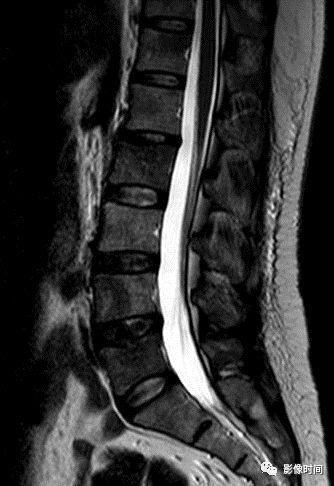

8牙膏征

牙膏征(Toothpaste sign)

牙膏征是指在矢状位脊柱影像中,脱出的椎间盘突入椎管内并向下游走,形似被挤出的牙膏而得名。

典型病例

矢状位 T2WI 像示脱出的椎间盘突入椎管,形似被挤出的牙膏,呈牙膏征(箭示)。

引用自:https://radiopaedia.org/ articles/ toothpaste-sign